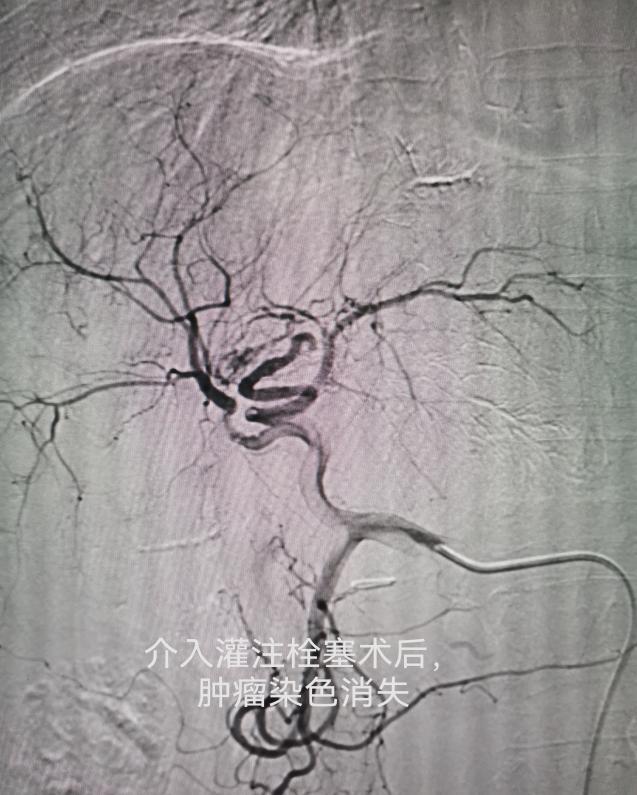

车能雨教授病例展示:

病例一:刘先生,男,55岁,患肺癌,经过三次介入微创手术+三次细胞治疗+靶向治疗,肺癌缩小90%,全身脊柱转移灶得到控制硬化,全身剧痛消失,处于NED状态。